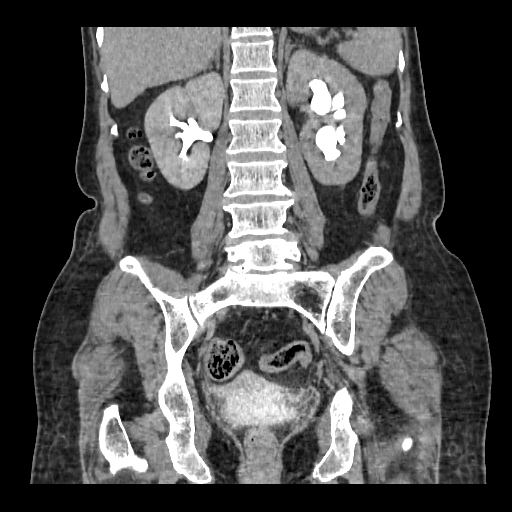

A 50 years old woman with suffering from left sided PUJ obstruction